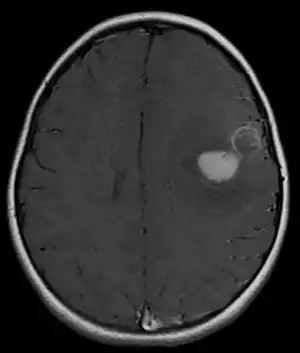

| Primitive neuroectodermal tumor of the central nervous system in a 5-year-old |

Several analysis can be used to determine the presence of the disease. Physical examinations showing papilledema, visual field defects, cranial nerves palsy, dysphasia, and focal neurological deficits are evidences for possible tumor.[2] PNETs can also be spotted through computed tomography (CT) and magnetic resonance imaging (MRI).[2] In images produced by MRIs, an irregular augmentation among a solid mass will indicated the presence of tumor.[3] However, the results of MRIs are usually ambiguous in defining the presence for this specific tumor.[2] In CT scans, the presence of PNETs will be indicated by an elevated density and an increase in volume of the brain.[2] The CT scan can also show calcification,[3] which is present in 41-44% of PNET cases.[2] Since the tumor can be replicated in other parts of the nervous system through the cerebrospinal fluid (CSF), a CSF analysis can also be conducted.[2] A spinal MRI is a fourth type of analysis that is useful in investigating the level of tumor propagation to the spinal cord.[2]